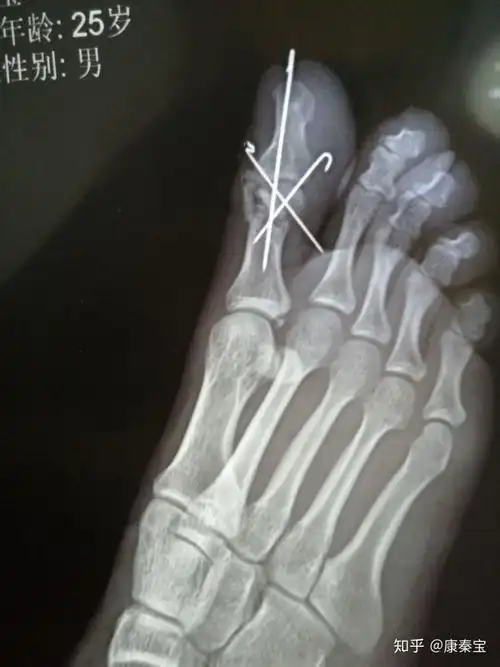

2014-03-23 刘辉东 医师 第二脚趾骨折4月了.

足拇指近节远端粉碎性骨折,微创手术解决大问题!